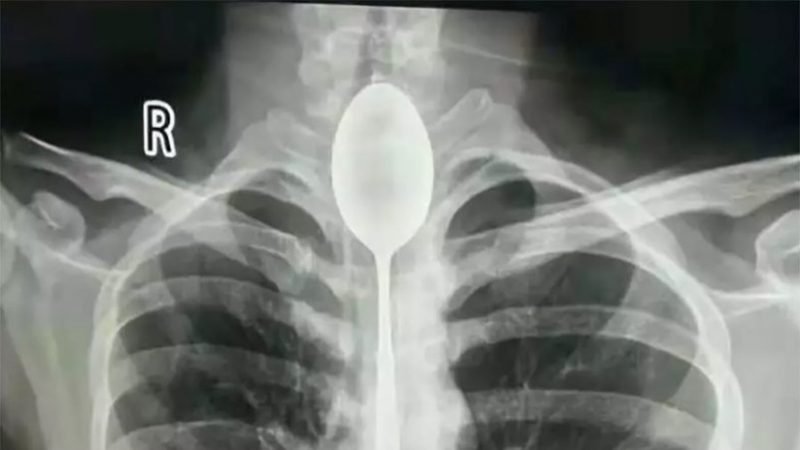

Se tragó una cuchara de 20 centímetros y logran retirársela un año más tarde

Médicos chinos tuvieron que sacar una cuchara de 20 centímetros que estuvo atorada durante un año en el esófago de un joven.

En una cosa Zhang tuvo suerte: no se necesitó intervención quirúrgica para sacarle el cubierto. Luego de realizarle una radiografía, los médicos extrajeron el objeto metálico al paciente de 26 años por vía bucal. Todo ese tiempo, un poco más de dos horas, el joven estuvo totalmente anestesiado, según un comunicado del hospital.